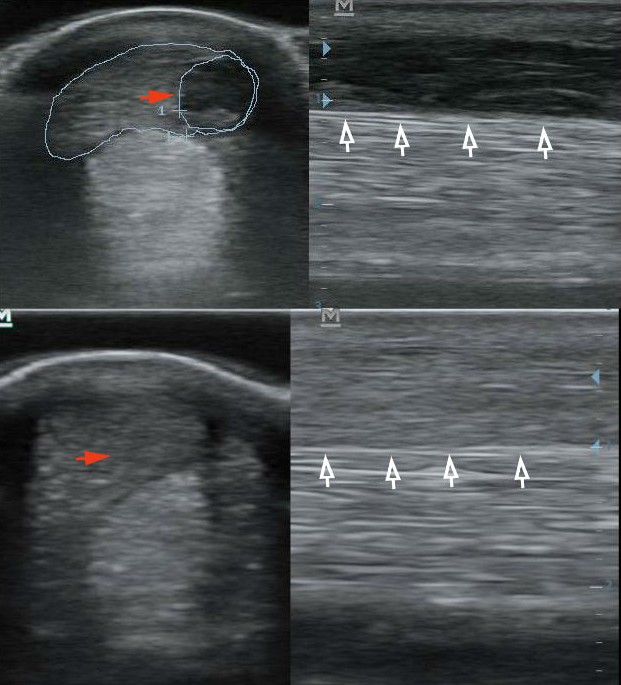

A bal felső oldalon a felületes ujjhajlító ín friss sérülése (bekarikázva, piros nyíl). A jobb felső sarokban az ín sérülése hosszmetszetben (fekete sáv a fehér nyilak felett). A bal alsó, keresztmetszeti kép három hónappal az őssejt kezelés után (a piros nyíl a sérülés helyére mutat). A defekt teljesen kitöltődött. A jobb alsó sarokban hosszmetszetben látjuk a kitöltődött defektet (a fehér nyilak fölött). Az ín szerkezete még nem teljesen megfelelő.